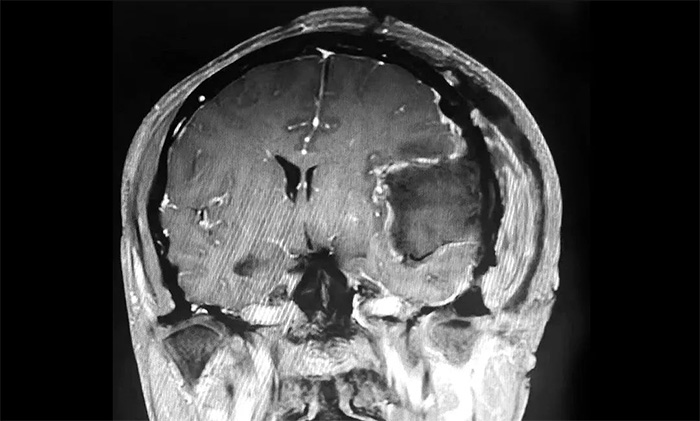

入院后,患者收治于神经内科4A病区。完善针对性检查后,经多学科综合会诊,患者左侧额颞部实性占位,最大直径约6.0公分,体积如鸭蛋大小,考虑左侧额颞部脑膜瘤。

▲ 肿瘤体积如鸭蛋大小

▲ 肿瘤顺利切除

手术取左侧额颞顶部入路,在显微镜下,沈建康主任与于耀宇主任通力协作,仔细分离肿物周边密集的神经血管,逐步分块切除肿物及附着的硬膜。切除肿瘤后,术区瘤腔未见活动性出血。历时5小时,手术顺利完成,留取病理标本送检。